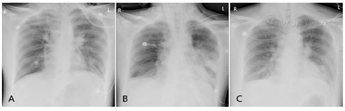

治疗期间患者病情演变(图2),多次复查胸部X线片(图3),10天后好转。随访患者哮喘控制症状、胸部CT(图4)及肺功能(图5)。检查局限性:患者病情危重,由于ECMO仪器特殊性及管路因素,未完善肺功能及胸部CT检查。

诊断依据:①支气管哮喘病史多年;②典型症状:伴哮鸣音的呼气性呼吸困难、胸闷、气促;③体征:双肺可闻及广泛的哮鸣音,三凹征阳性;④胸部X线片:双肺透亮度增加,提示过度通气;⑤特异性变应原检测:IgE增高;⑥动脉血气:低PaO2伴高PaCO2。